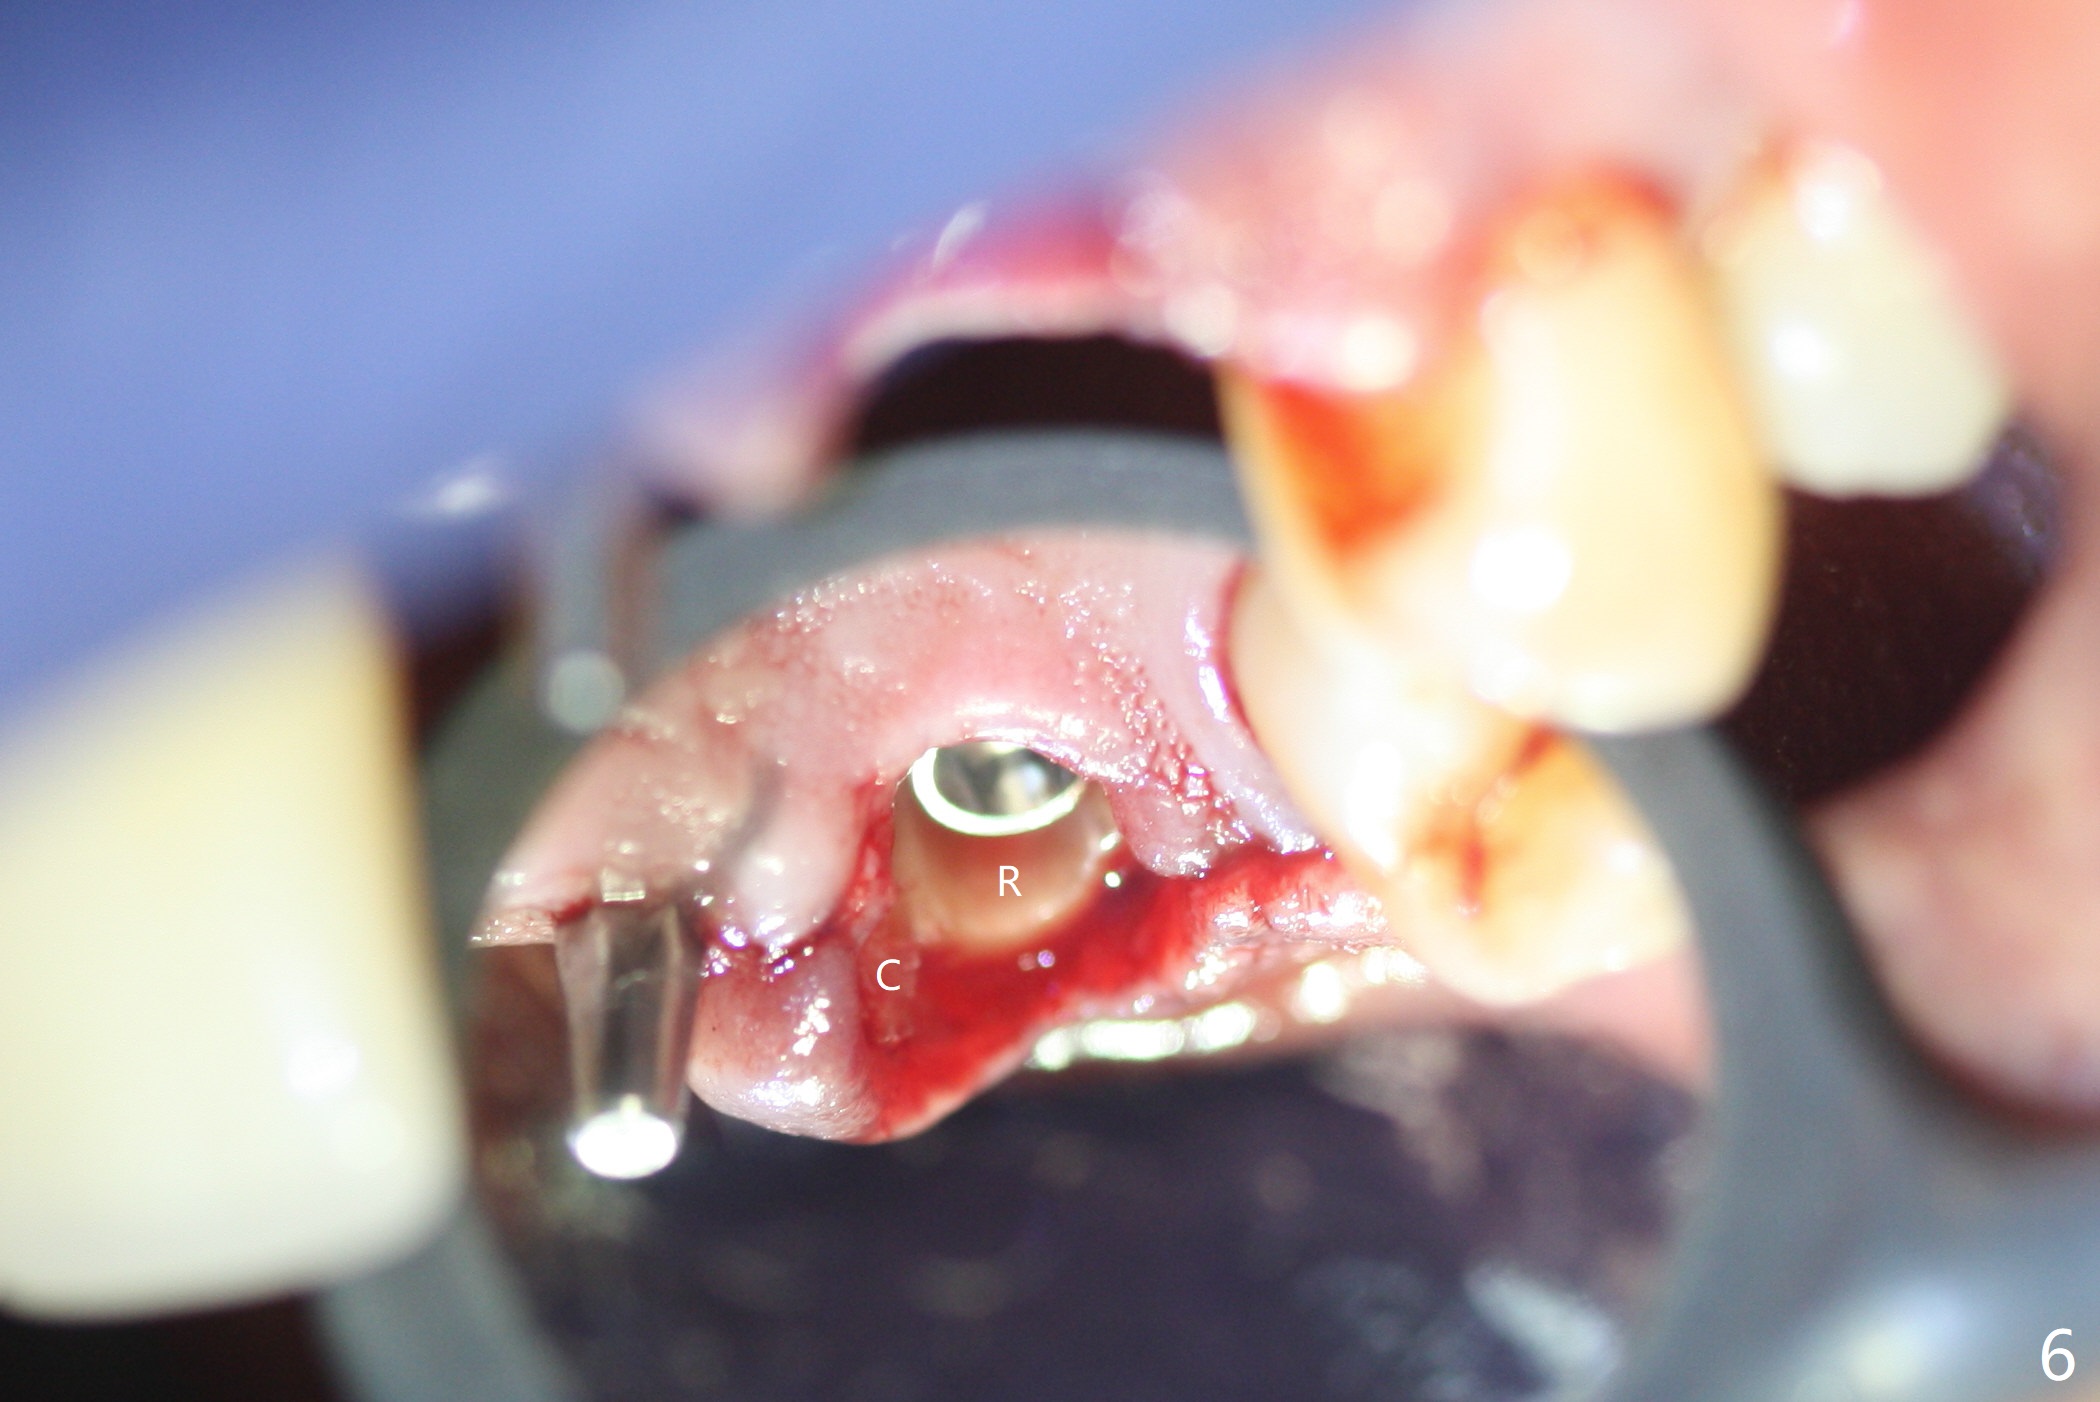

The buccal plate at #10 undergoes atrophy 9 months post immediate implant (Fig.1 *). To prevent the same post-extraction complication at #11, a technique called socket shield is going to be adopted. The buccal portion of the root (Fig.2-6 R, half-moon shaped) remains in place while a 3.5x13 mm implant is placed in the palatal portion of the socket (>50 Ncm). In fact the root is trimmed slightly subcrestal (Fig.6 C). It is assumed that there will be no or minimal bone resorption as long as the periosteum between the buccal plate and the remaining buccal root is not disturbed after tooth removal. After placement of a 4.5x15 degrees A (2mm) angled abutment and Vanilla graft (Fig.7 *), an immediate provisional is fabricated (using a central incisor crown form for #10 because of extra wide space of #11, Fig.8). There is no buccal plate atrophy at the canine 11 days postop (Fig.9). There is smooth transition from the grafted bone to the native bone 4.5 months postop (Fig.10). The buccal plate remains non-atrophic at the canine 4.5 months postop (Fig.11,12). CT taken 1 month post cementation shows that the implants at #10 and 11 are placed somewhat lingually (Fig.13,14 L (*: socket shield)). Gingival swelling is noted (Fig.15 *) with +Bleeding On Probing (^) 8 months post cementation (at the time of #21/24 impression). It appears that the socket shield (Fig.16 S) causes infection and loss of bone graft (*). The shield will be removed with an oblique accessory incision to save the papilla between #10 and 11 (Fig.17 black line). Prepare PRF for sticky bone (x1).